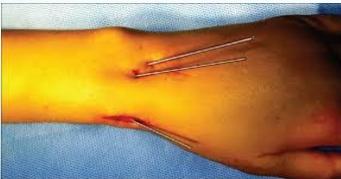

K-wire (Kirschner Wire)

- Indications:

- Fixation of Pediatric fractures

- Small bone fractures in adults

- Advantages:

- Easy to apply

- Easy to remove

- Disadvantages/Problems:

- Not stable alone

- Infection if end left outside skin